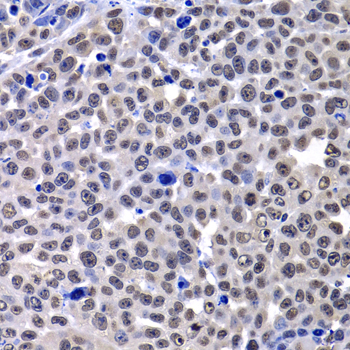

Immunohistochemistry of paraffin-embedded human kidney using mH2A1 antibody.

Immunohistochemistry of paraffin-embedded human kidney cancer using mH2A1 antibody.

Immunohistochemistry of paraffin-embedded human stomach using mH2A1 antibody.

Immunohistochemistry of paraffin-embedded mouse lung cancer using mH2A1 antibody.